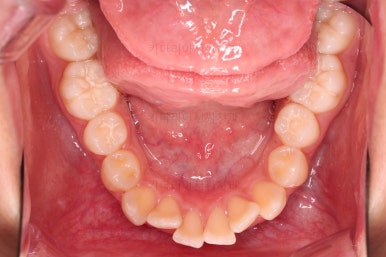

1. 초진 시 입안의 모습 평가

부산치아교정치과 키다리아저씨치과에 처음 내원했을 당시의 입 안의 모습입니다.

전반적으로 윗니가 나와있는 양상이고요.

앞니는 뻐드러져 있네요.

아래 앞니는 위로 솟구쳐 올라서 윗니 뒤쪽을 강하게 치고 있는 과개교합 양상이었고요.

위아래 앞니쪽이 삐뚤어져 있는 상태였습니다.